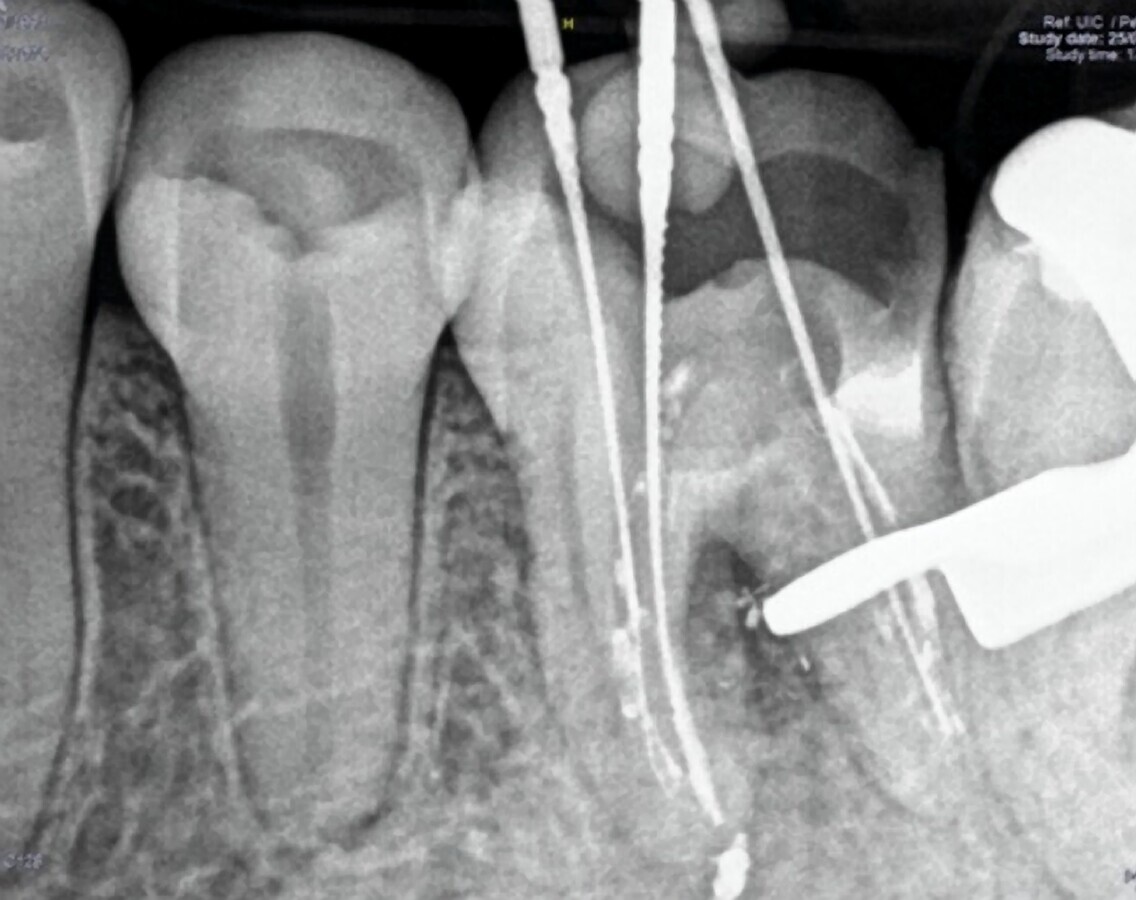

Fig. 6. Remoción de la gutapercha y localización de la longitud de trabajo.